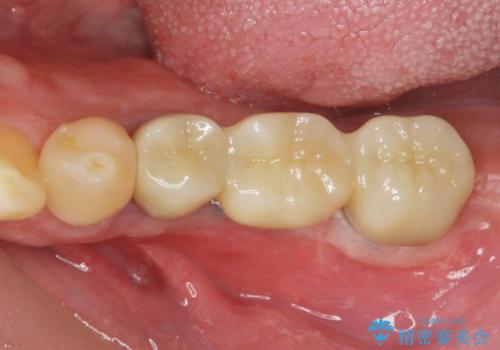

臼歯部インプラント・再補綴

- 失ってしまった左下の奥歯にインプラント治療を受けたいと来院されました。

左下の欠損部には強度・表面性状に優れるストローマン社製インプラントを埋入し、合わせて噛み合う上顎の歯もクラウン再補綴による整備を行い安定した咬合関係の構築を目指します。

- 122.1万円(仮歯×5・ストローマンインプラント×2・アバットメント×2・ジルコニアクラウン×5・ゴールドインレー)費用は治療当時の料金となります

歯を失った期間が長くなると、対合する歯が伸びてくることによる補綴スペースの狭小化がしばしば見られます。

今回左下にインプラント治療を行うにあたり、対合する上顎の歯もいっしょに治療を行ったことで安定した咬合関係を構築することができました。